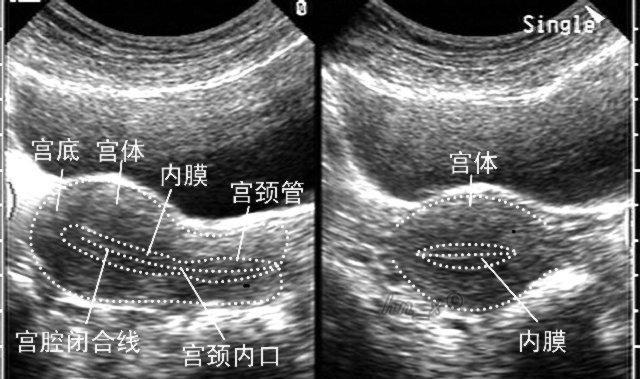

看正常的女性月经周期不同时期内膜的厚度变化,是需要根据女性具体处于月经周期的什么时期来看。女性处于不同的月经周期内,正常的子宫内膜厚度各不相同。子宫内膜功能层是胚胎植入的部位,受卵巢激素变化的调节,具有周期性增殖、分泌和脱落性变化,具体组织学变化,一般将月经周期分为增生期、分泌期和月经期三个阶段(以一个正常月经周期28日为例):

由于女性的子宫内膜厚度在月经周期的不同时期厚度是不一样的,所以如果要做检查,建议女性最好在月经干净后三天作用,到医院做阴道B超,这样可以了解自己的子宫内膜具体厚度为多少。在超声检查时,若医生发现子宫内膜过厚,可判断为异常。子宫内膜如果过厚,容易造成痛经,且受精卵难以成功着床;若子宫内膜过薄,则容易造成月经量少,甚至会影响到女性的排卵功能。女性如果在检查过程时发现子宫内膜厚度异常,则需要及时进行相应的治疗,以免影响到自己的生育功能。